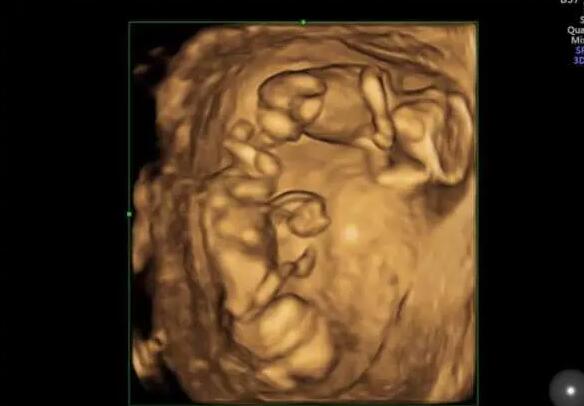

试管婴儿取卵可以做几次?专家解读试管婴儿需要取卵几次。试管婴...